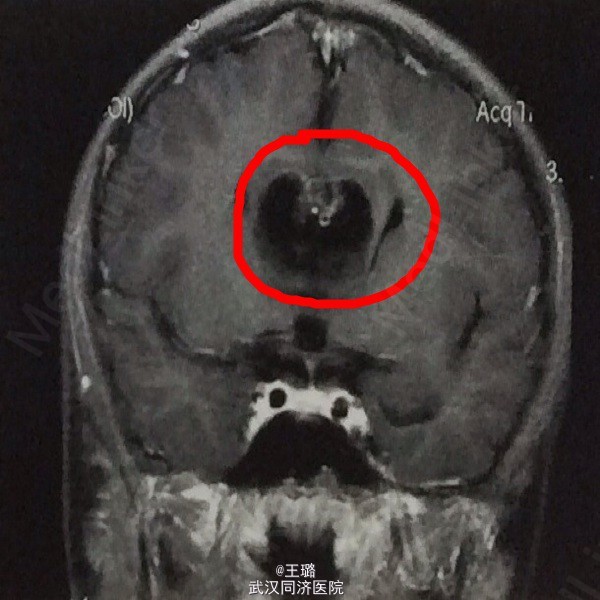

胼胝体缺如伴脂肪瘤一例

患者,2岁,因头痛、癫痫入院,体检神经反射微弱,病理反射未引出,皮肤感觉障碍,其余无异常。实检示:血常规正常,血生化白蛋白降低,肝肾功能正常。MRI示:双侧脑室分离,未见胼胝体结构,胼胝体区呈短T1、长T2信号病灶,中线居中。考虑为胼胝体缺如病瘤样物填充,遂行开颅切除,病检示:脂肪瘤。胼胝体缺如伴脂肪瘤是最常见的颅脑先天性畸形,属神经管闭合畸形,如有中胚层的脂肪组织渗入则会引起脂肪瘤。